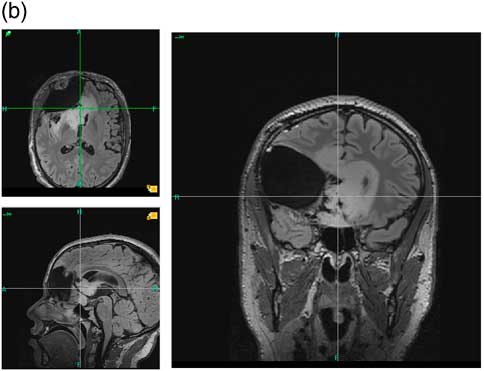

L’examen anatomopathologique a conclu à un gliome diffus de bas grade de l’adulte, de phénotype oligodendroglial, de grade II (Reference Kleihues and W.9). Une IRM au décours de cette première intervention a permis de vérifier le caractère très partiel de cette première résection (IRM du 25 septembre 2012 – Figure 1-b), et compte tenu de l’enjeu oncologique, une seconde intervention est programmée, de nouveau en condition éveillée, afin de compléter la première exérèse. Cette intervention a lieu quatre mois après la première, au mois d’octobre 2012.

Figure 1b IRM du 25 septembre 2012. Préopératoire de la seconde intervention Séquences axiale, sagittale et coronale FLAIR. On n’observait pas sur la séquence T1 de rehaussement après injection de gadolinium.